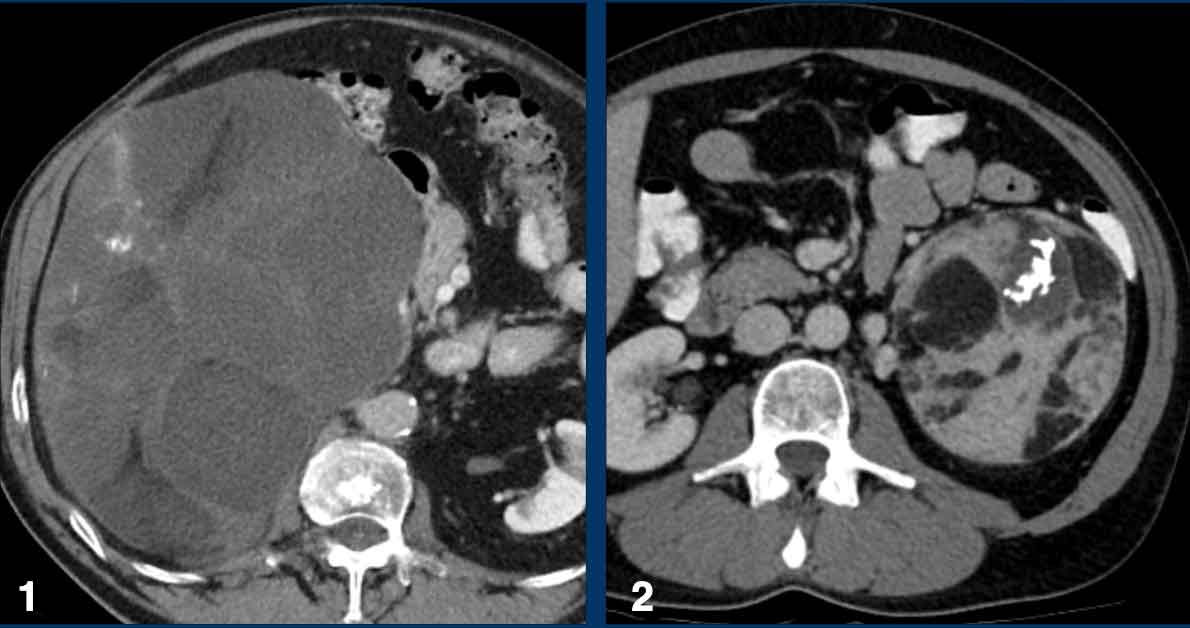

Indeterminate lesions > 4 cm

The maximum diameter of the adrenal mass is predictive of malignancy.

In particular, lesions > 4 cm are more likely to be either metastases or adrenocortical carcinomas.

Adrenal mass size is important for two more reasons.

The overall prognosis is better for small adrenocortical carcinomas and smaller tumors are easier to resect by minimally invasive surgical techniques.

Therefore, the recommendation for an indeterminate adrenal mass > 4 cm in size and no history of cancer is surgical resection -in most cases without biopsy - in order to timely treat a possible primary adrenal cortical carcinoma [3,9].

The next cases are examples of indeterminate lesions > 4 cm.

All were incidentally discovered in patients without a history of cancer.

All diagnoses were histologically proven and showed a wide variety of both benign and malignant tumors.

Metastasis of an adenocarcinoma Metastasis of an adenocarcinoma

The image shows a heterogeneous ill-defined mass larger than 4 cm.

There is a hypo-enhancing center, which is probably the result of central necrosis.

In this particular case a biopsy was performed and revealed an adenocarcinoma, probably from primary lung carcinoma.

Surprisingly, extensive imaging analysis, including FDG PET-CT, did not detect a primary tumor, however.

Adrenocortical carcinoma Adrenocortical carcinoma

The image shows a 67 mm heterogeneously enhancing relatively well defined lesion.

This proved to be an adrenocortical carcinoma, after resection.